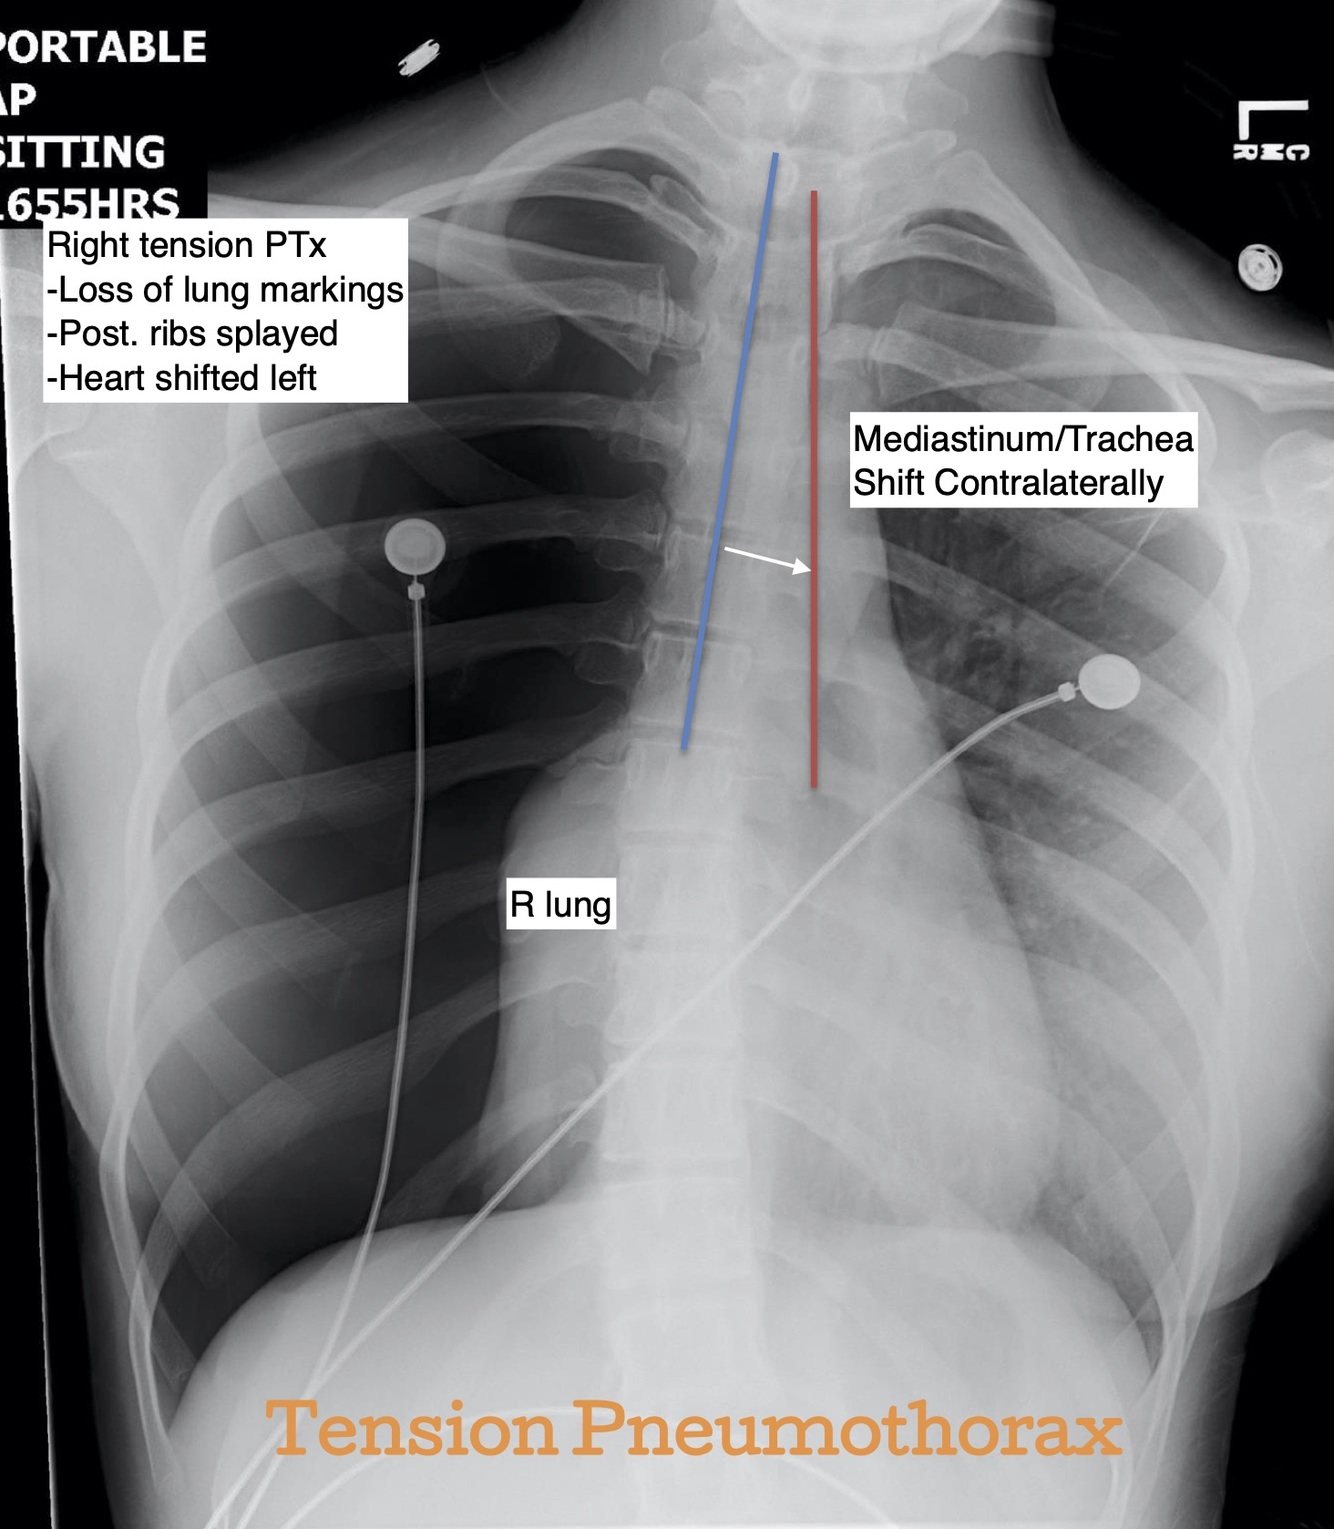

Tension Pneumothorax

Signs of tension PTx:

Trachea

Normally found in the midline.

Abnormalities: